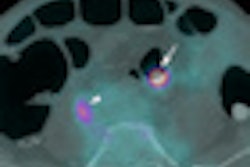

VeraLook is available in Europe under CE Mark approval; in the U.S., it is pending clearance by the U.S. Food and Drug Administration (FDA). The software detects and highlights potential polyps during CTC examinations, and the newest version features performance improvements including a greater than 5% increase in the sensitivity of potential polyp detection and a 20% reduction in false positives, according to iCAD.